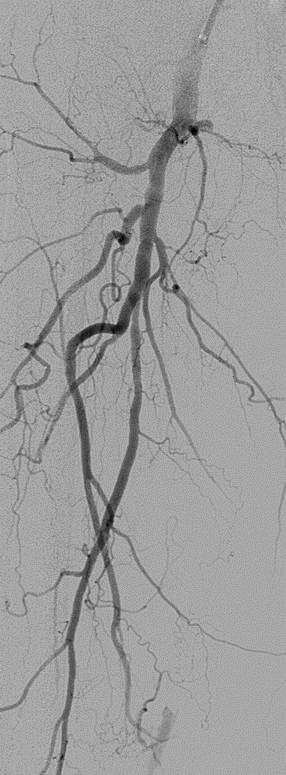

★ Case 1

noproximal stump in SFA,>250mm

★ Case 2

significantdistal collaterals